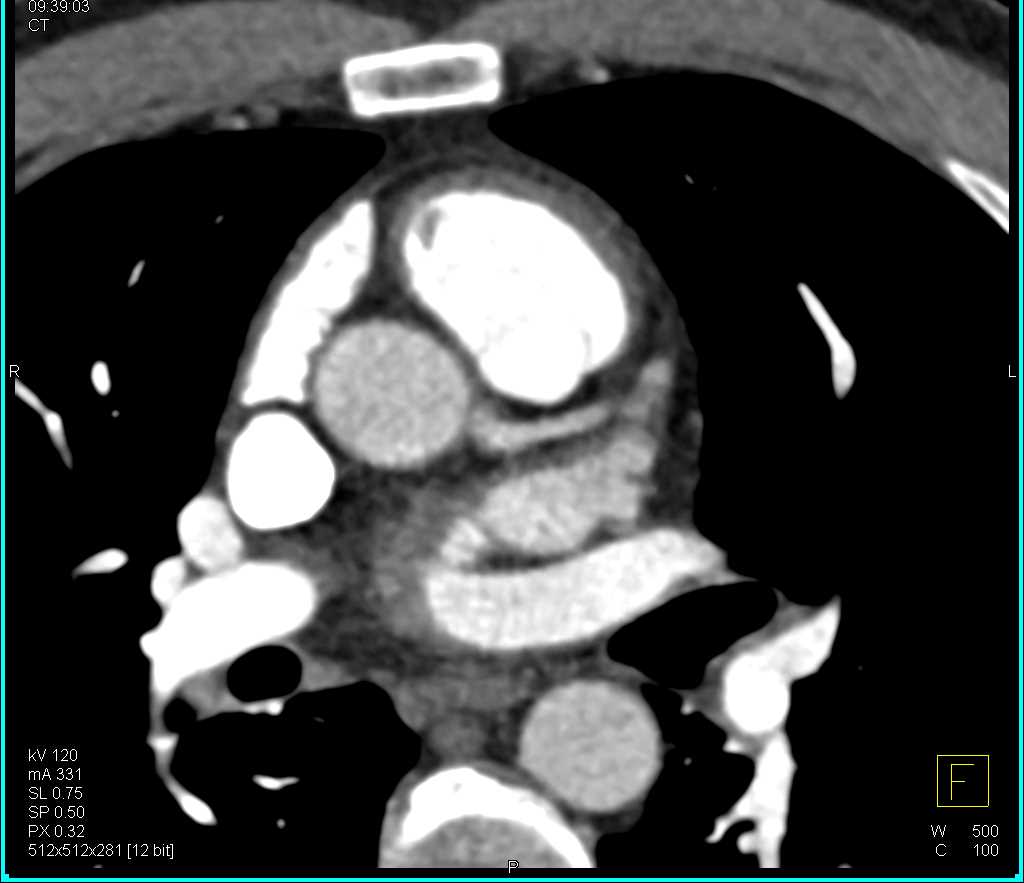

Clot in Right Atrium off the Indwelling Catheter